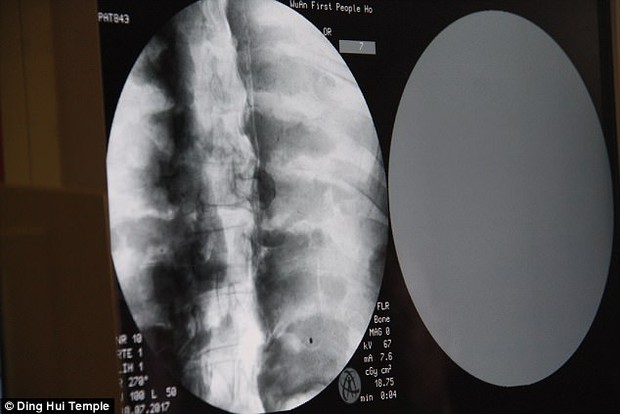

Theo tờ Daily Mail, đầu tháng 7 năm 2017, các nhà khoa đã tiến hành chụp CT để "nhìn thấu" bên trong xác ướp mạ vàng của nhà sư Ci Xian nổi tiếng Trung Quốc. Nhà sư Ci Xian được cho là một nhà sư được vạn dân kính trọng, ông đã đi từ Ấn Độ cổ đại đến Trung Quốc cổ đại để quảng bá Phật giáo.

Ngày 8/7/2017, trước sự chứng kiến của các nhà sư, giới truyền thông và nhiều người dân, các nhà khoa học đã tiến hành chụp CT xác ướp nhà sư Ci Xian.

Ban quản lý của ngôi chùa đã sắp xếp một buổi chụp CT xác ướp nhà sư Ci Xian vào ngày 8 tháng 7 năm 2017

Mọi người đều bàng hoàng khi các bác sĩ cho biết nhà sư Ci Xian vẫn còn nguyên bộ xương, và một bộ não hoàn chỉnh. Tức xác ướp này đã được bảo quản gần như nguyên vẹn sau hơn 1.000 năm. Điều này khiến giới khoa học sửng sốt với kỹ thuật ướp xác thời bấy giờ.

Bác sĩ Wu Yongqing nói với kênh Pear Video sau khi tiến hành chụp CT cho xác ướp: "Chúng tôi có thể thấy xương của ngài ấy khỏe mạnh như một người bình thường. Hàm trên, răng trên, xương sườn, xương sống và tất cả các khớp đều vẫn nguyên vẹn. Thật không thể tin được khi thấy điều này".